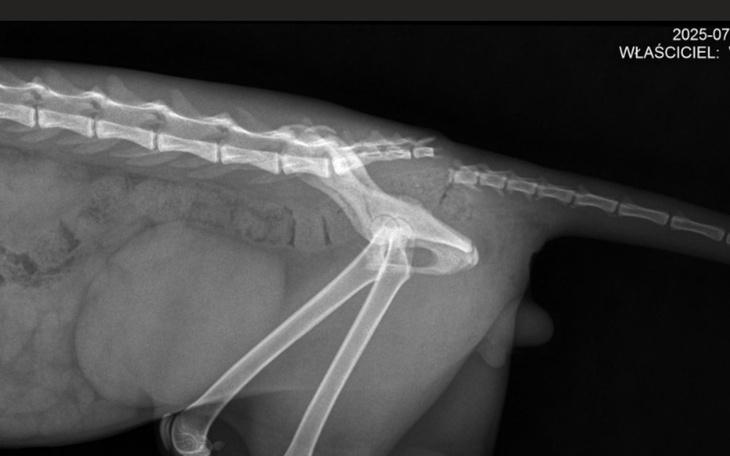

Niestety, ale los był dla niego okrutny - kotek jest połamany i potrzebuje operacji 😞 Co tu więcej mówić, nie tak miało być, nie tak powinny wyglądać pierwsze koteczkowe lata życia 😞 leczenie Łatka i operacja zostały wycenione na około 2000zł. Prosimy o wsparcie finansowe - pomóżmy temu kotu, aby stanął na łapki.